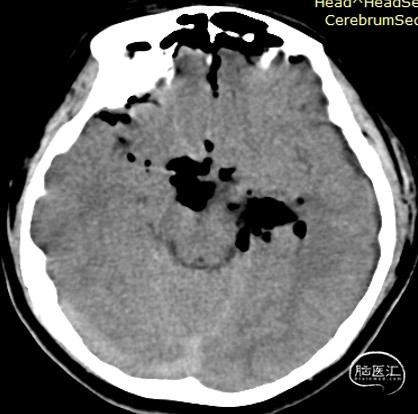

术前影像:

左侧海马旁回海绵状血管瘤。